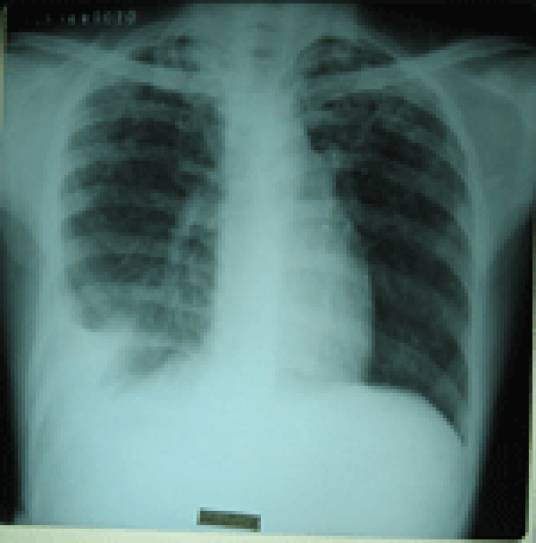

活动性肺结核指新涂阳、复治涂阳和新涂阴患者。活动性肺结核是指痰涂片阳性者,证明有结核分枝杆菌排出,病灶属于活动期,胸片上常有斑片状阴影或是结核空洞,或者播散病灶,说明结核分枝杆菌繁殖活跃,毒力强。治疗四个月,复查痰涂片和痰培养阴性者,胸片提示钙化,纤维化,硬结等,说明结核控制,无传染性及临床症状。无活动性即不是活动性肺结核。